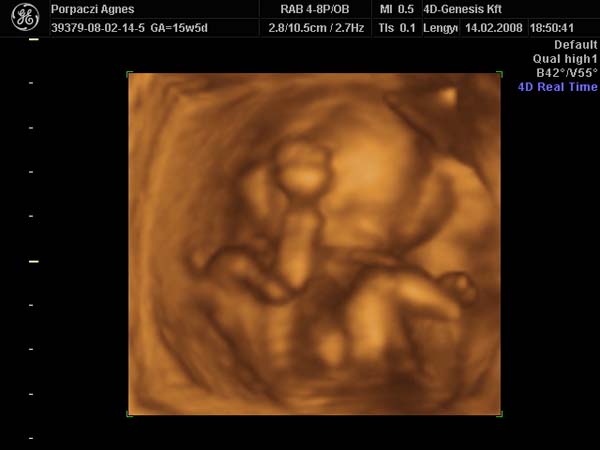

Bence 18 hetesen

A doki szerint pufók kislány